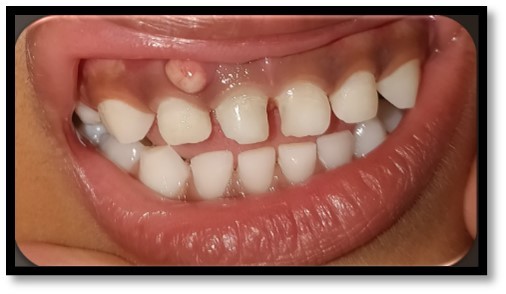

- Gingival abscess- Associated with a tooth with a deep carious lesion

- Draining fistula- Associated with a tooth with a deep carious lesion

- Extraoral swelling- Associated with a tooth with a deep carious lesion

- Abnormal tooth mobility